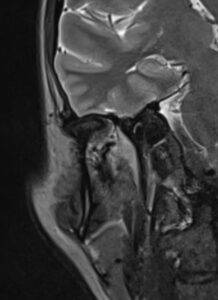

MRT Ohr

Wenn eine Beurteilung der Anatomie des Ohres mithilfe einer MRT-Untersuchung erfolgen soll, dann handelt es sich hierbei um eine MRT Kopf Untersuchung.

Was sieht man bei einer MRT Ohr?

Der große Vorteil der MRT liegt neben ihrer hohen Präzision im exzellenten Weichteilkontrast. Daher ist sie insbesondere bei der Beurteilung von Tumoren, Entzündungen und Nekrosen des Knochens und der Weichteile den übrigen bildgebenden Verfahren häufig deutlich überlegen. Selbst kleinste, sonst nicht sichtbare Veränderungen können oftmals per MRT sichtbar gemacht werden.